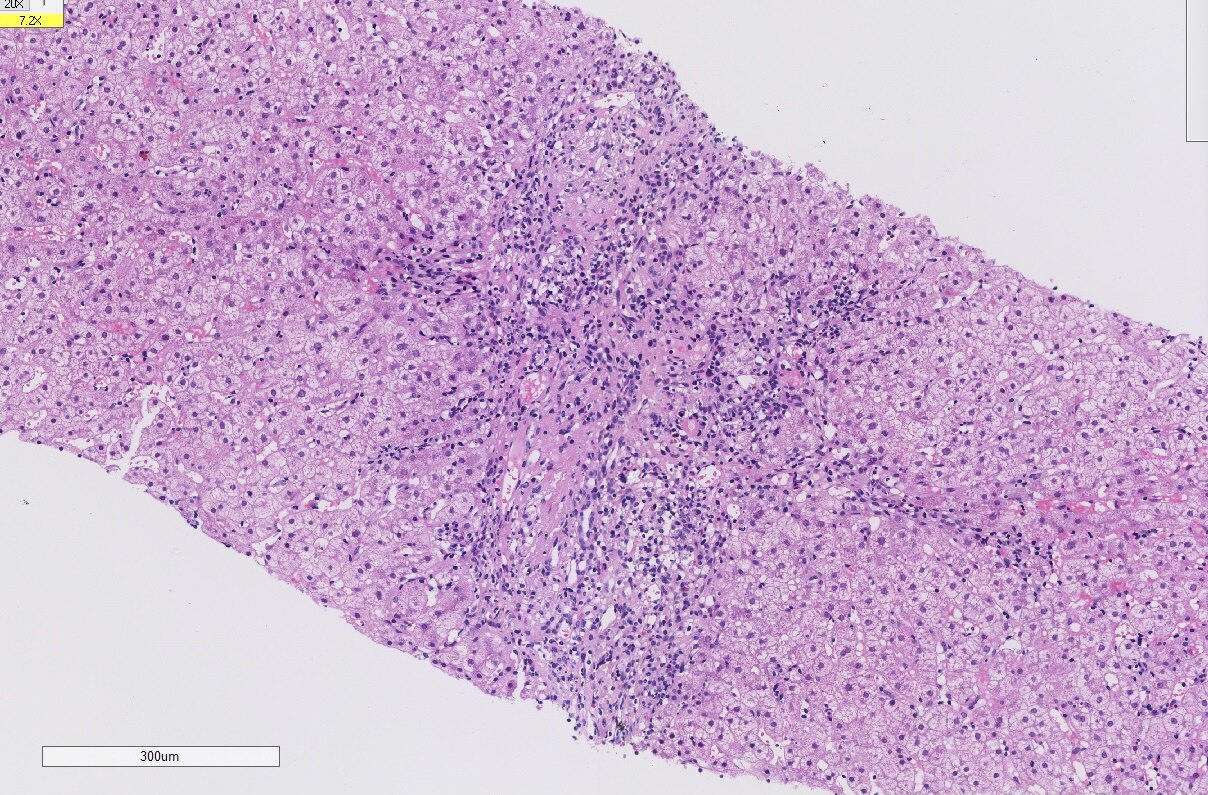

肝活检的意义

经常碰到长期肝功能异常的患者,常规检查做了仍不能找到原因。这时候我会建议进行肝活检,虽然有时候肝活检仍然不能给予一个确切的诊断,但是起码能够知道病变的部位在哪?是肝细胞损伤为主,胆管损伤为主,还是两者兼有,这样我们就能根据不同的患者给予不同的治疗方案,做到精准治疗和个体化治疗!